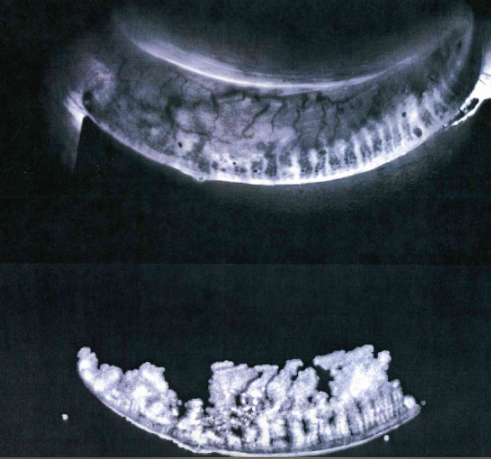

Above you can see the glands disappearing on the right side of the lower lid in this 11 year old boy who spends 3 hrs a day on an electronic device.